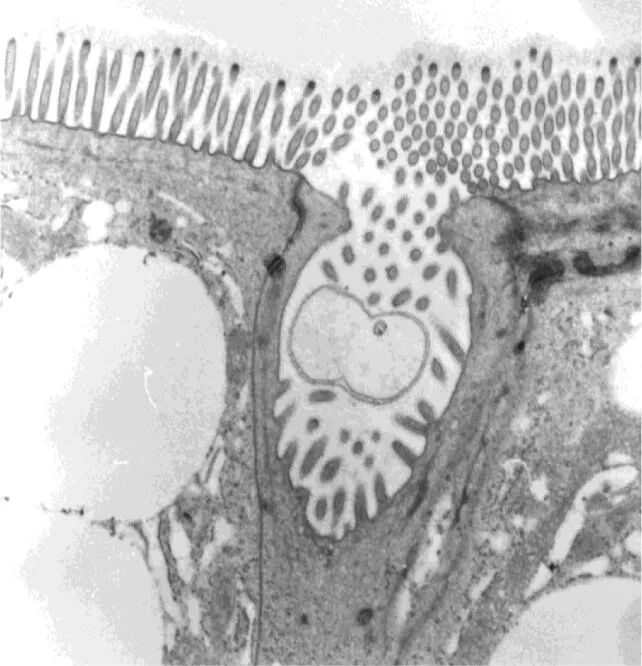

一项新研究找到了答案:缅甸蟒的肠道壁上有一种过去从未发现的特殊细胞,能把多余的钙、磷和铁以颗粒的形式沉积,并通过排泄系统排出体外。它们和其他负责吸收营养的肠道细胞长得不太一样,形状更狭窄,有更短的微绒毛,顶端的褶皱形成一个隐窝。

这些细胞顶端有个隐窝,里面会生成矿物质颗粒 | 参考资料[2]

为了确认这些细胞的作用,科学家给蟒蛇喂了无骨猎物,发现这些细胞的隐窝空空的,不会生成富含矿物质的颗粒。但如果给蟒蛇喂食带骨猎物,或者在无骨猎物的基础上额外补充钙,这些细胞的隐窝中会生成大量矿物质颗粒;而且,蟒蛇的粑粑里完全没有骨头碎片,说明已经被彻底消化了。